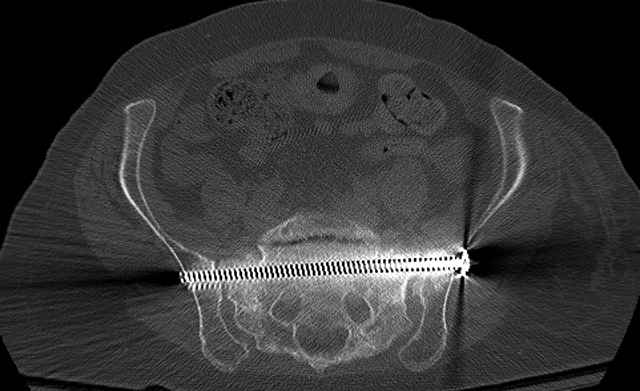

Here are a recent patient’s example slides...

54 yo Female Fell c/o Pain

Initial Films

?Instability on Exam - Limited by Pain

NonOp Initial Mgmt

3 Months After Fall

Continued Pain & Immobility

(+) Instability to Compressive Manual Exam

Pelvic CT Scan - 3 Months After Fall

Sacral Injuries

Ramus Fractures

Percutaneous Fixation

(B) Ramus-Retrograde

2 TransIliac-TransSacral

Upper Segment